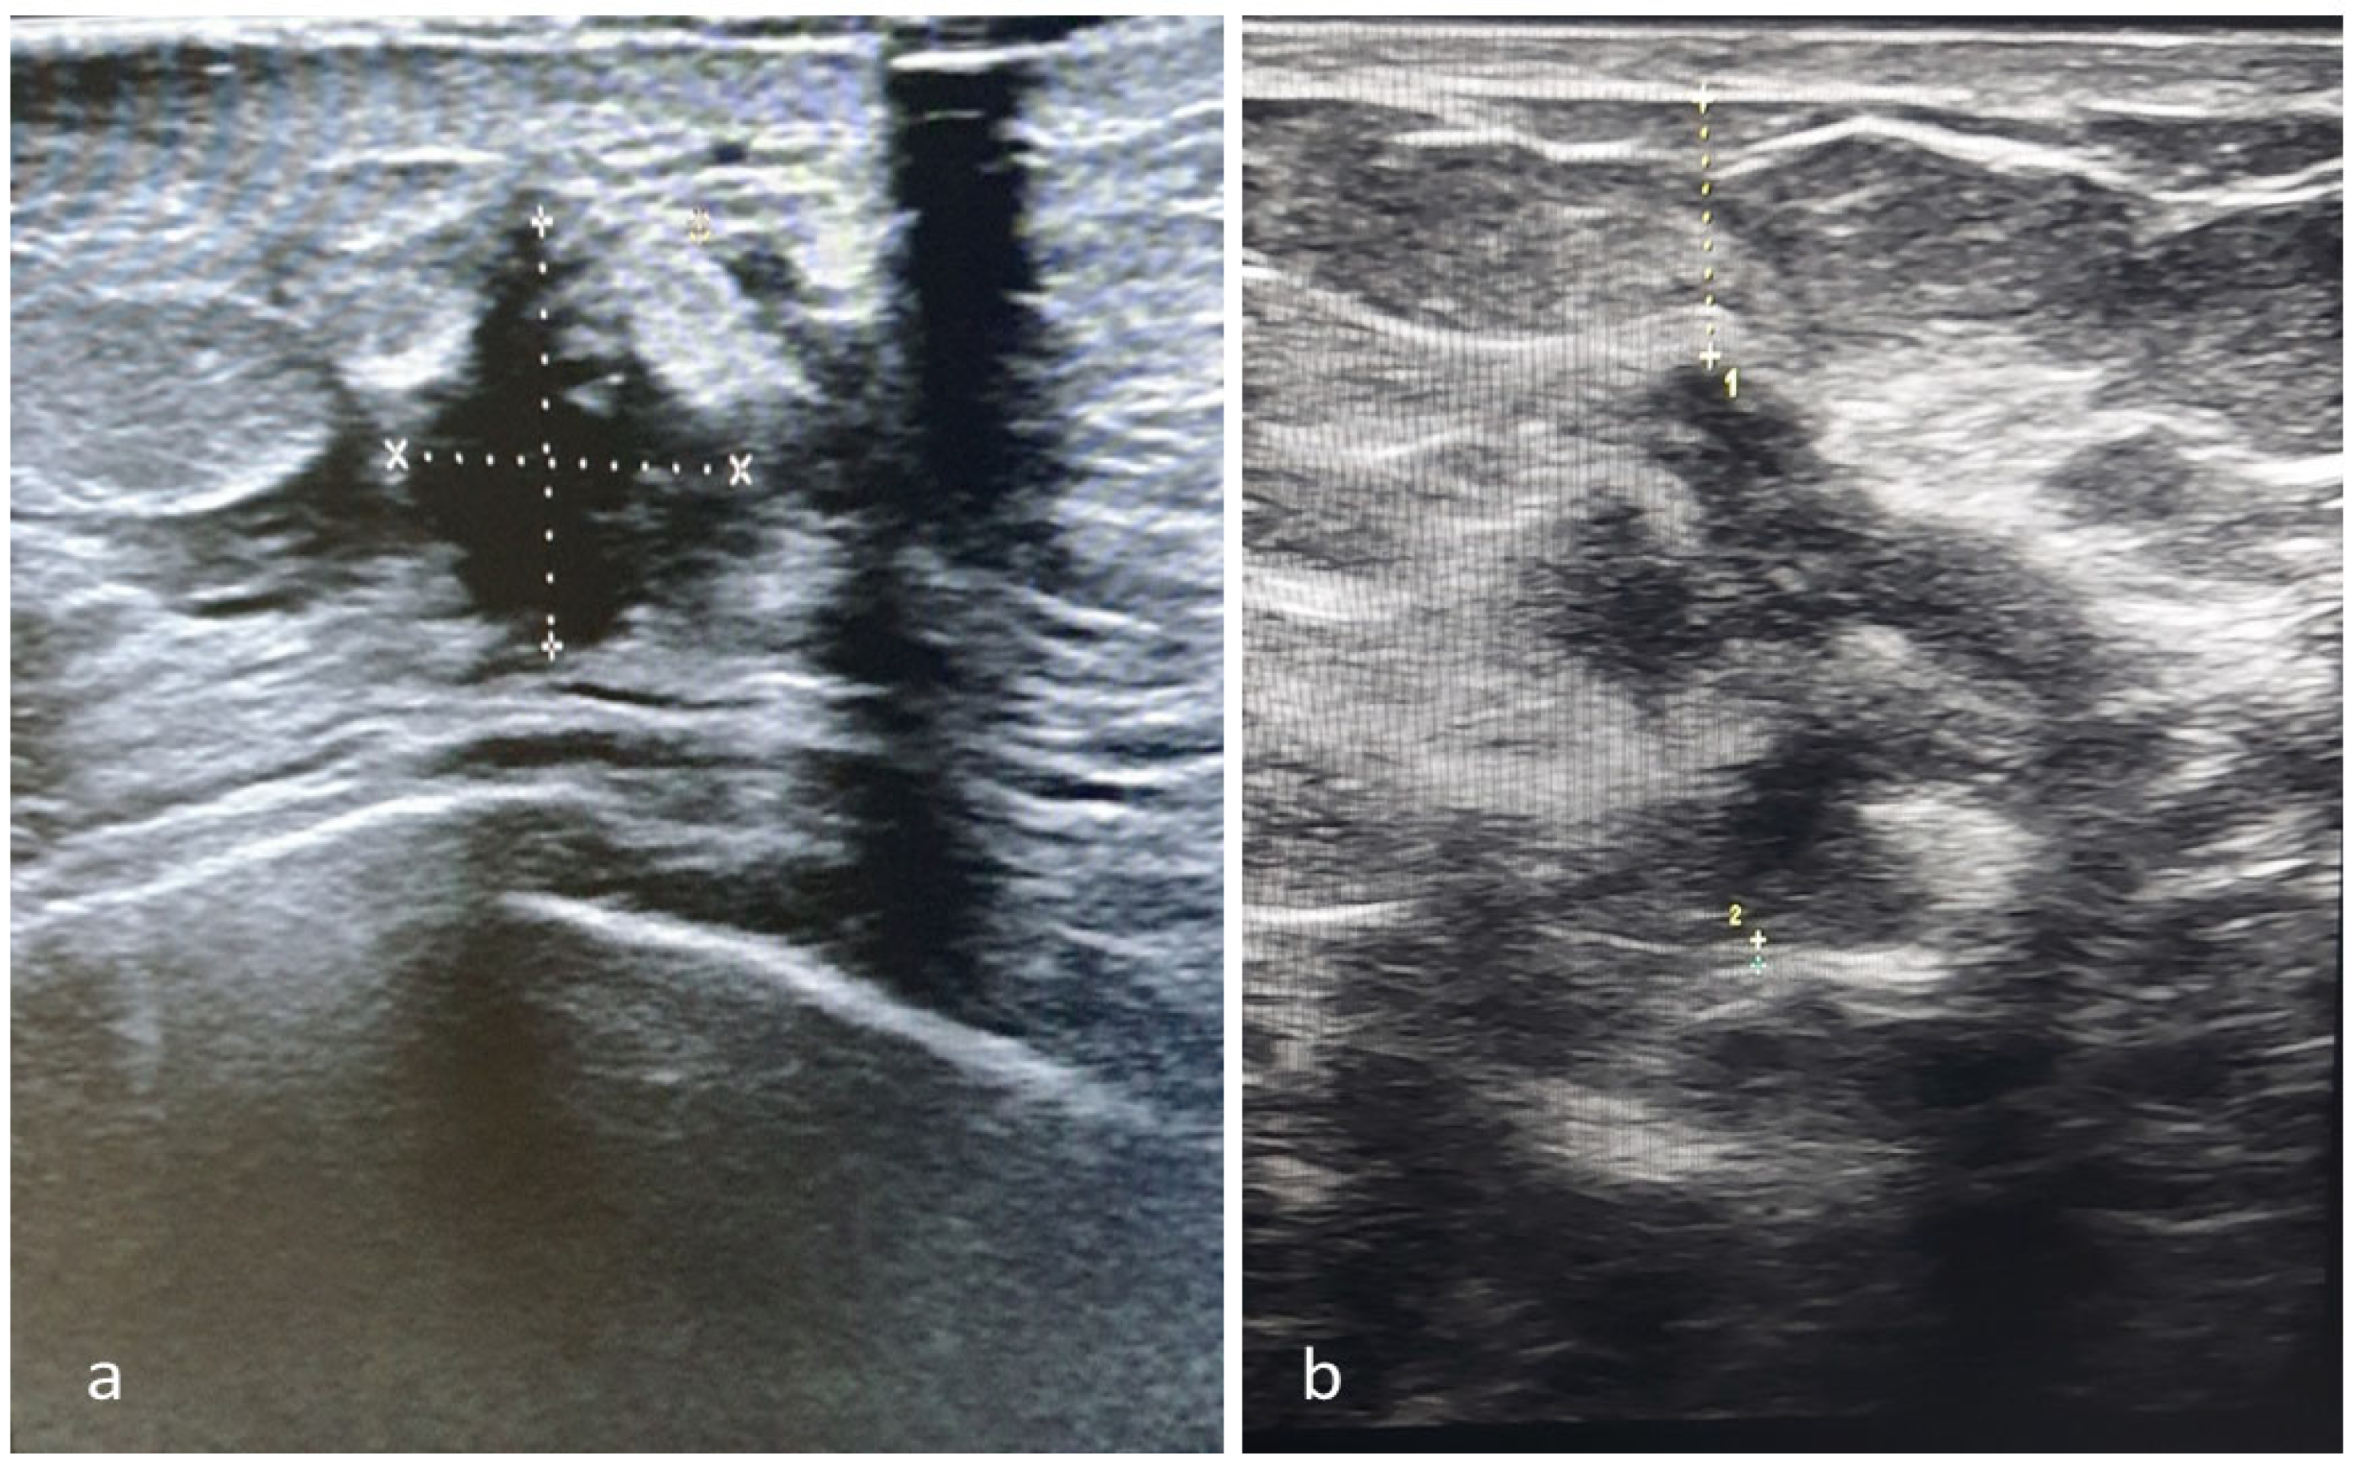

3. Technique Description

3.1. Diagnostic Procedure